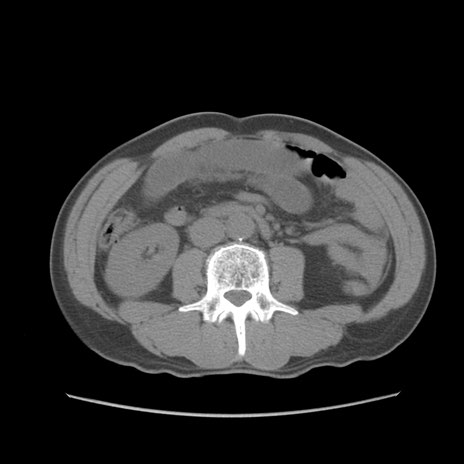

症例56 CT(横断像)

脂肪ウインドウ